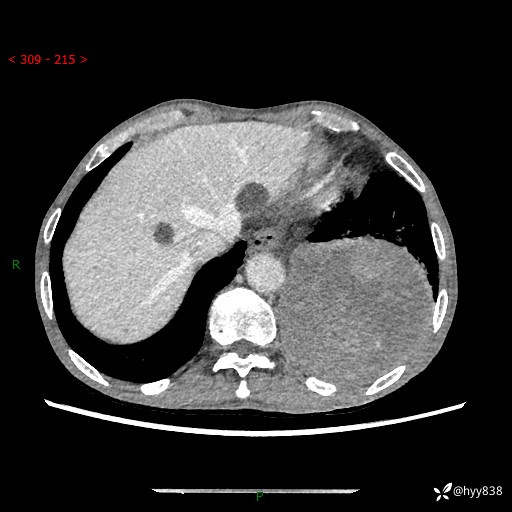

77岁/男,腹痛2月,CT发现左肺占位1天。巨大肿块,肺内或肺外来源…结果公布~

主诉:腹痛2月,CT发现左肺占位1天

现病史:患者于2025年9月间断左下腹胀痛,在当地镇卫生院行彩超检查考虑泌尿系结石,行止痛排石对症治疗未见明显好转;1天前腹痛症状加重,至当地市第三人民医院行CT检查:左肺下叶巨大团块状软组织影,考虑肿瘤性病变,建议增强CT检查;左侧胸腔积液;纵膈内淋巴结肿大;双肺肺气肿;右肺中叶纤维灶。为进一步求治,来我院就诊。

胸部CT平扫+增强